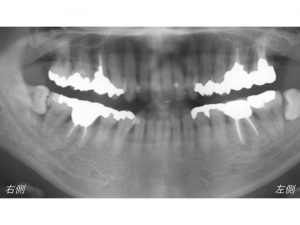

まず症例を見てみましょう。

下顎右側の奥歯が虫歯担っている状態です。

ここが虫歯です。

わかりにくいので拡大してみてみましょう。